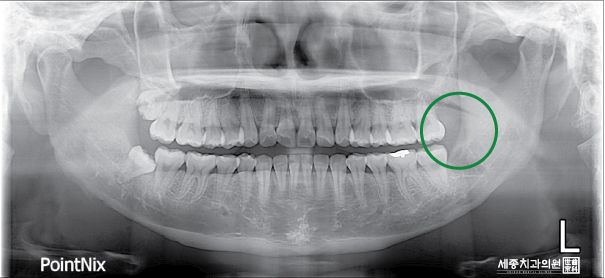

저는 스케일링을 하면서 마취를 진행하였고 사랑니 왼쪽 위아래? 모두 발치를 하였습니다.

일주일 후 실밥 제거를 한다고 하시는데 가능하다면 실밥 제거할 때 남은 사랑니 두 개도 뽑고 싶습니다!